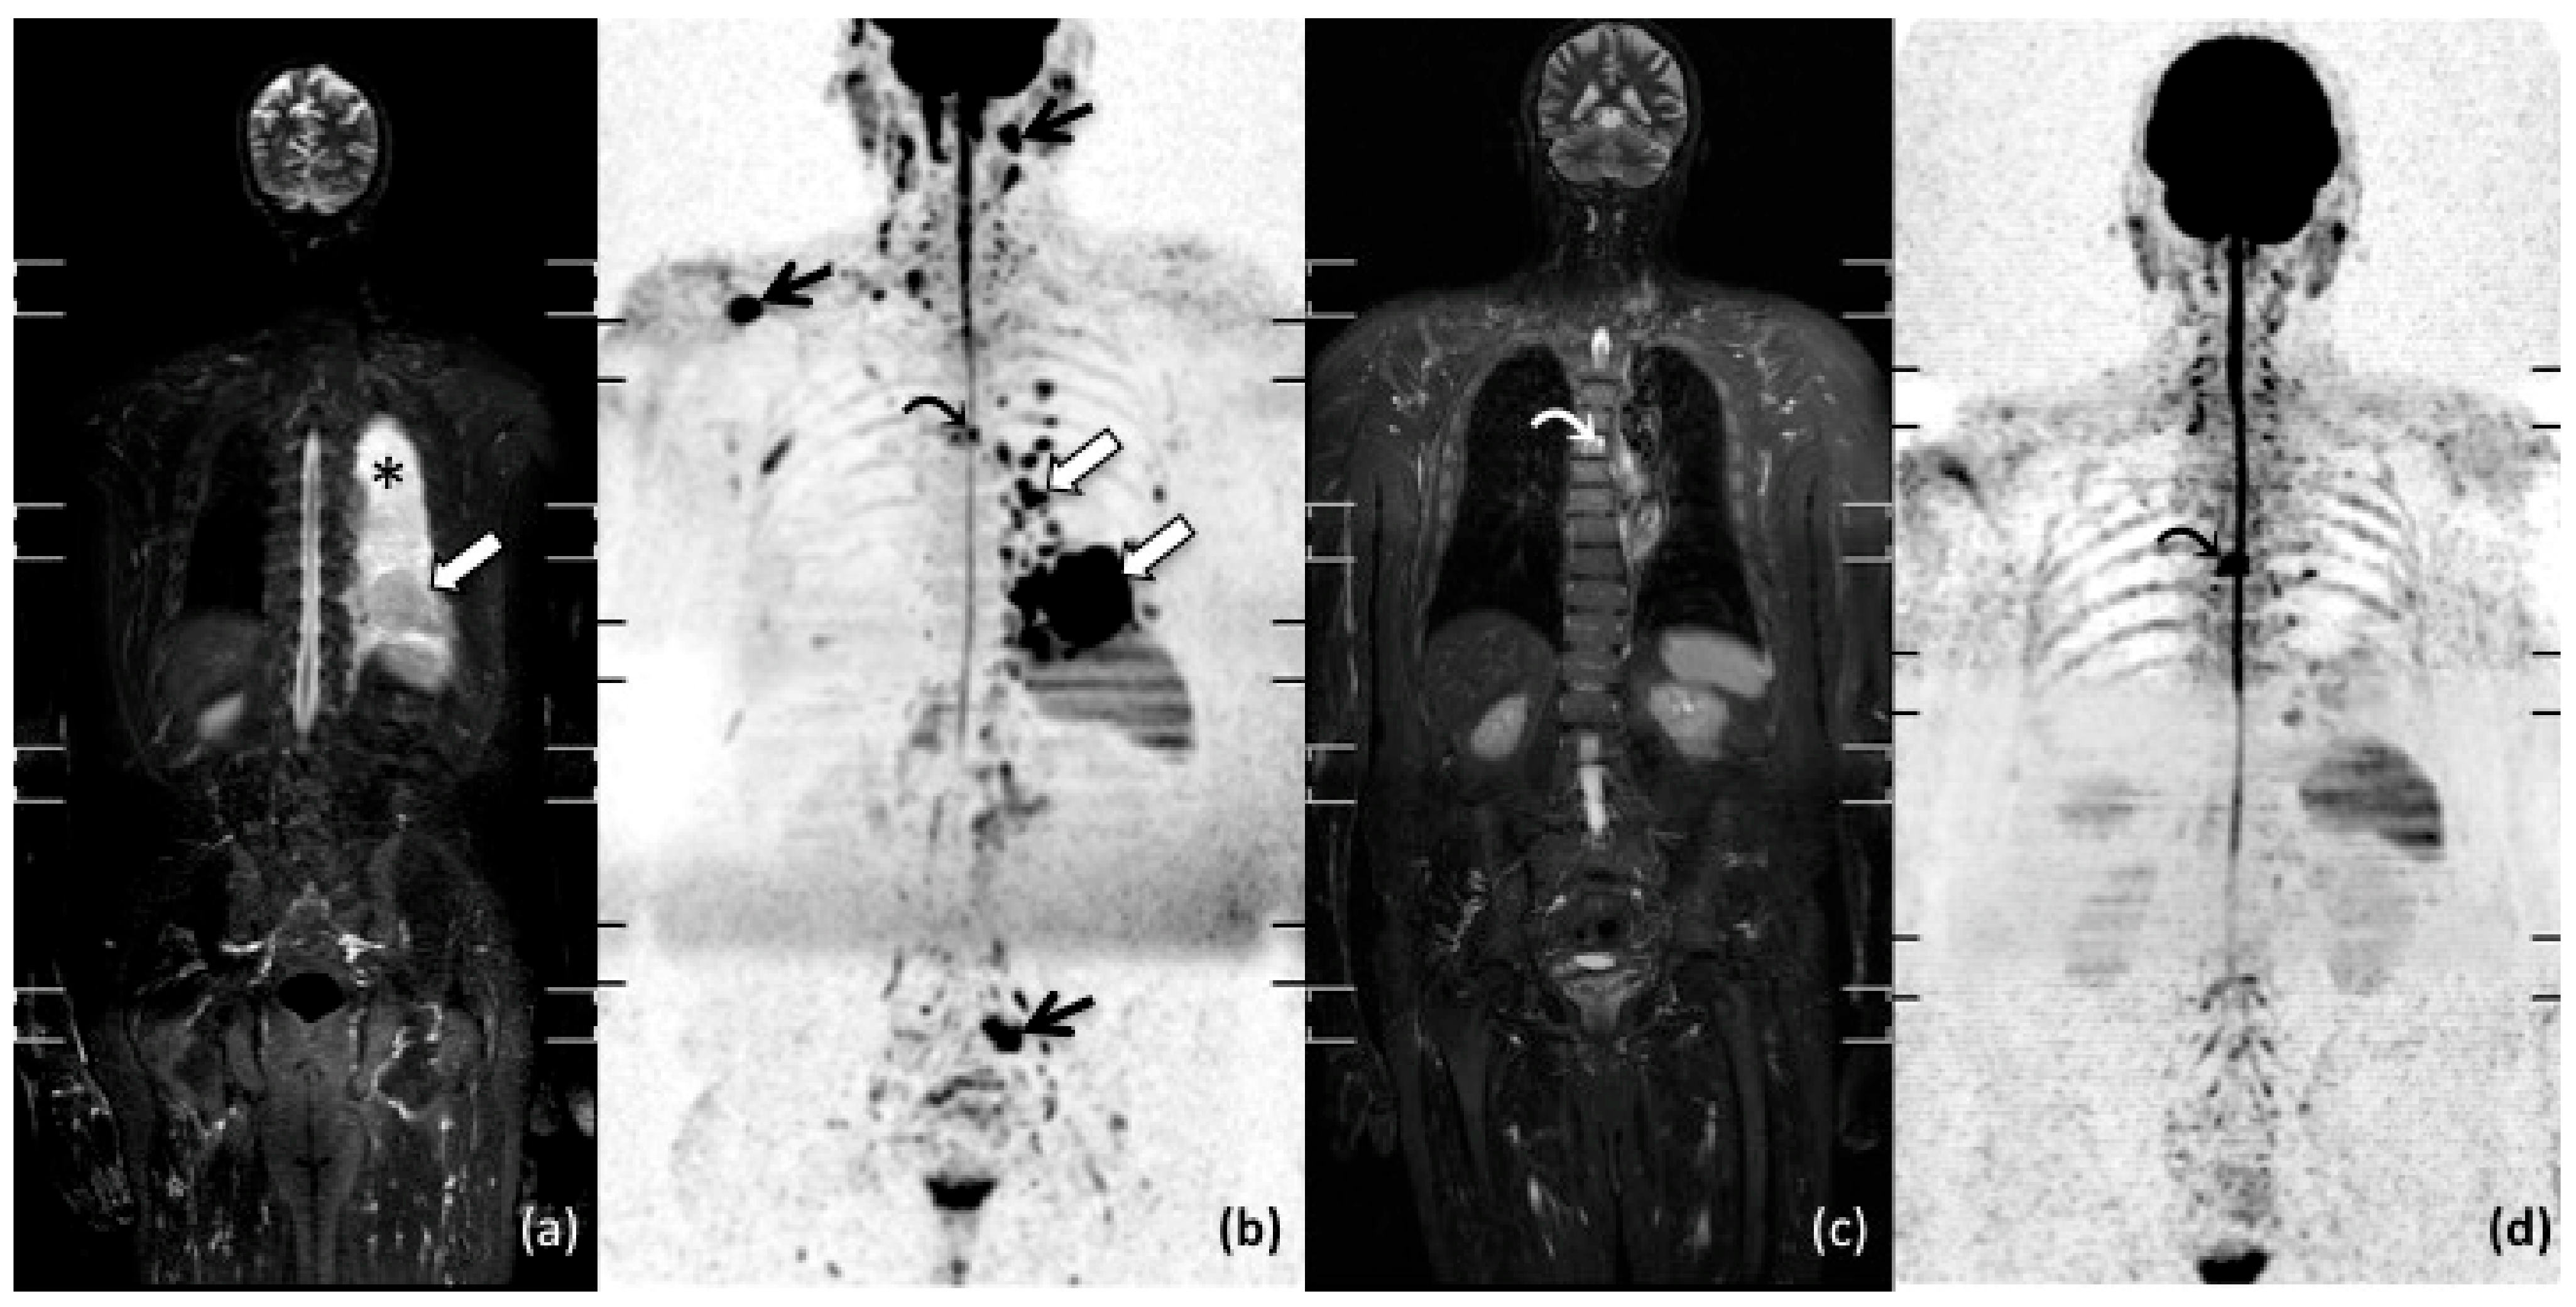

- Albano, D.; Patti, C.; Matranga, D.; Lagalla, R.; Midiri, M.; Galia, M. Whole-body diffusion-weighted MR and FDG-PET/CT in Hodgkin Lymphoma: Predictive role before treatment and early assessment after two courses of ABVD. Eur. J. Radiol. 2018, 103, 90–98. [Google Scholar] [CrossRef]

- Horger, M.; Claussen, C.; Kramer, U.; Fenchel, M.; Lichy, M.; Kaufmann, S. Very early indicators of response to systemic therapy in lymphoma patients based on alterations in water diffusivity—A preliminary experience in 20 patients undergoing whole-body diffusion-weighted imaging. Eur. J. Radiol. 2014, 83, 1655–1664. [Google Scholar] [CrossRef] [PubMed]

- Latifoltojar, A.; Punwani, S.; Lopes, A.; Humphries, P.D.; Klusmann, M.; Menezes, L.J.; Daw, S.; Shankar, A.; Neriman, D.; Fitzke, H.; et al. Whole-body MRI for staging and interim response monitoring in paediatric and adolescent Hodgkin’s lymphoma: A comparison with multi-modality reference standard including 18F-FDG-PET-CT. Eur. Radiol. 2018, 29, 202–212. [Google Scholar] [CrossRef] [PubMed]

- Lin, C.; Itti, E.; Luciani, A.; Zegai, B.; Lin, S.-J.; Kuhnowski, F.; Pigneur, F.; Gaillard, I.; Paone, G.; Meignan, M.; et al. Whole-Body Diffusion-Weighted Imaging With Apparent Diffusion Coefficient Mapping for Treatment Response Assessment in Patients With Diffuse Large B-Cell Lymphoma. Investig. Radiol. 2011, 46, 341–349. [Google Scholar] [CrossRef] [PubMed]

- De Paepe, K.; Bevernage, C.; De Keyzer, F.; Wolter, P.; Gheysens, O.; Janssens, A.; Oyen, R.; Verhoef, G.; Vandecaveye, V. Whole-body diffusion-weighted magnetic resonance imaging at 3 Tesla for early assessment of treatment response in non-Hodgkin lymphoma: A pilot study. Cancer Imaging 2013, 13, 53–62. [Google Scholar] [CrossRef] [PubMed][Green Version]

- Mayerhoefer, M.E.; Karanikas, G.; Kletter, K.; Prosch, H.; Kiesewetter, B.; Skrabs, C.; Porpaczy, E.; Weber, M.; Knogler, T.; Sillaber, C.; et al. Evaluation of Diffusion-Weighted Magnetic Resonance Imaging for Follow-up and Treatment Response Assessment of Lymphoma: Results of an 18F-FDG-PET/CT–Controlled Prospective Study in 64 Patients. Clin. Cancer Res. 2015, 21, 2506–2513. [Google Scholar] [CrossRef] [PubMed]